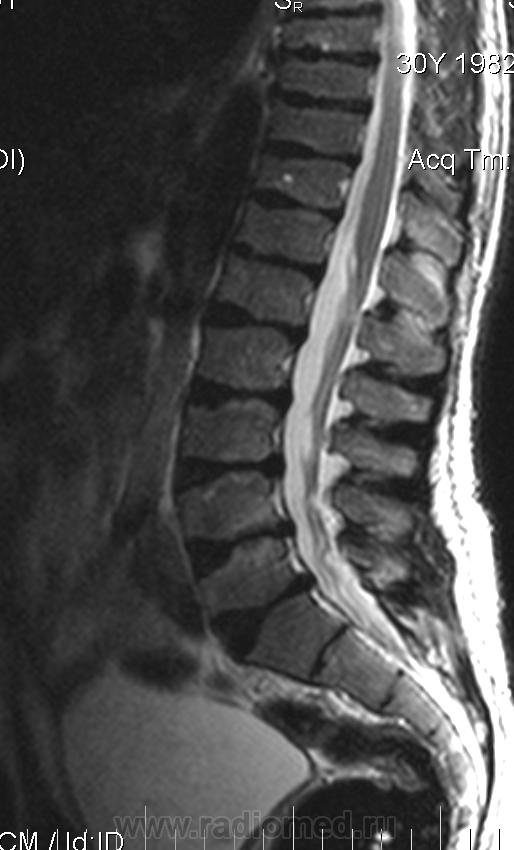

Мужчина 30 лет, рост 151см

Уважаемые колллеги, помогите, пожалуйста. Изменение формы тел позвонков. Остеохондропатия?

Изменения позвонков типичны для спондилоэпифизарной дисплазии.

Для спондилоэпифизарной дисплазии типична деформация позвонков по типу "переднего языка", платиспондилия, низкорослость, при Шойерман-Мау деформация позвонков другого типа.

деформация по типу "переднего языка" - это "шестиугольная" форма позвонка как в данном случае на уровне поясничного ОП?